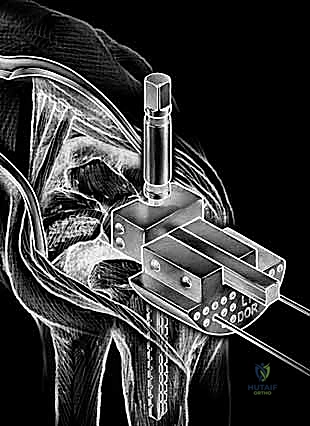

Carpal preparation requires exacting precision. Using the Maestro system as the archetype, the carpal resection guide is positioned to allow resection of 2 to 3 mm of the capitate head. It is provisionally held in position with two 0.062-inch Kirschner wires. The first wire is placed into the capitate neck and the second into the metaphysis of the third metacarpal, ensuring that the guide is perfectly parallel to the third metacarpal axis. With proper placement, the ulnar guide wing will lie close to the triquetrum–hamate articulation, and the radial wing will bisect the scaphoid at its distal third.

With the wrist held in neutral, the radius is scored through the cutting slot in the guide to provide a reference for the distal radial resection. The thumbscrew on the carpal resection guide is loosened to allow insertion of the radial resection guide boom. Following radial resection, the scaphoid, capitate head, hamate edge, and triquetrum are resected at a precise 90-degree angle to the axis of the forearm jig. The trial carpal plate is provisionally determined by the curvature and width of the remaining proximal carpal surface; it must lie flush with the hamate and proximal capitate surfaces. Unlike older designs, it is not always necessary to attempt fusion of the distal pole of the scaphoid to the surrounding carpus. The Maestro Wrist has a provision to replace the entire scaphoid using a carpal plate incorporating a modular radial augment, of which three separate sizes are available.

Following capitate reaming, the chosen carpal plate and stem are assembled and inserted into the capitate and seated onto the resected carpal surface. The carpal plate is anchored to the carpus with a radial screw that optimally does not penetrate the second metacarpal, and a second screw placed ulnarly into the hamate. This construct ensures stable distal fixation while avoiding the deleterious lever arm of a long metacarpal stem. Trial reductions are performed to assess stability, range of motion, and impingement. Once kinematics are confirmed, the definitive ultra-high-molecular-weight polyethylene (UHMWPE) body—which is direct compression molded onto a cobalt chrome alloy radial body—is impacted. The capsule and extensor retinaculum are meticulously repaired to prevent extensor tendon bowstringing and provide a robust soft tissue envelope over the implant.